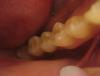

MamAnuta Опубликовано 31 октября, 2013 Поделиться Опубликовано 31 октября, 2013 Доброго времени суток, уважаемые специалисты!Заранее извиняюсь, за качество снимков - домашняя фотосессия завтра попробую запросить их по электронке с клиники. Сама проживаю в другом городе. Год назад мне установили имплантанты на нижней челюсти 2 шт на место 6 и 7 зуба справа (винтовые Ankylos)Коронки поставили только 29 окт (т.к. верхние зубы "провисли" и было принято решение их "повернуть" к центру и "поднять" чтобы не спиливать при установке коронок - это заняло 6 мес).При выборе материала коронок мне предложили либо металлокерамику либо циркониевые. Я выбрала цирконий, т.к. сказали, что получше... эстетичнее что ли... Если честно, я думала, что циркониевые зубы, да и вообще имплантантированные зубы, выглядят как настоящие, только без дефектов... У меня же получился вид своего собственного, но только леченого перелеченого (как будто был кариес во всю полость зуба и закрыт более светлой пломбой), а посередине кругленькие желтенькие пломбочки, закрывающие технологические отверстия.Вид никакой об эстетике вообще молчу - ее там нет... При установке коронок (их сделали две слитные, но в каждой коронке отдельное отверстие для фиксации) я сразу высказала сомнение в цвете жевательной поверхности, т.к. она сильно (на мой взгляд) отличалась от других своих зубов и от боковой поверхности самих коронок.На что врач сказал, что это такие технические нюансы - так изготавливается коронка. Но после консультации в соседнем кабинете с кем-то по телефону сказал, что можно сделать и по-другому, но надо будет доплатить по 12тыс за каждую коронку за изготовление абатментов - вроде так их называл (я не специалист, поэтому могу врать в терминах).И вообще я первый в его практике пациент, который предъявляет претензии к цвету жевательной поверхности зуба - мол все равно ее никому не видно...Я сказала, что раз по-другому сделать технически нельзя, то пусть ставит так как есть.Подгоняли очень долго - все что-то мешало при накусывании. Долго отпиливали то ли сверху зубы, которые полгода выпрямляли, чтобы не пришлось стачивать, то ли снизу зуб за 50 тыс - даже не поняла Вроде все подпили, все хорошо, отфотографировали... дали зеркало...На вопрос почему нельзя было подобрать цвет этой пломбы под цвет поверхности зуба, доктор вспылил и сказал, что не понимает, что мне не нравится, а потом вообще сказал чтобы я приходила в другой день и они все переделают, никакой доплаты не нужно, просто все будет менее надежно и практически выгнал меня из кабинета, не объяснив больше ничего (у него был уже следующий человек по записи). В связи с этим вопрос - как должны выглядеть нормальные коронки в моей ситуации?Действительно я слишком придирчива и это НЕВОЗМОЖНО сделать иначе технически? Тогда почему врач сказал что переделают за свой счет? Что они мне там сделают - уже даже и думать не хочется Просмотрела кучу фото в интернете циркониевых коронок и такого чуда как у меня нигде не нашла На самом деле хочется послушать профессионалов - может я зря на доктора обижаюсь? Но тогда странно, что за все это убожество надо платить ТАКИЕ деньги - 2 зуба обошлись более чем в 100тыс руб...Муж считает, что я придираюсь, хотя у самого год назад вставлено тоже 2 зуба в этой же клинике - на них не видно ничего - просто обычные нормальные зубы. Хочется объективности - прошу Вашей помощи Ссылка на комментарий

MamAnuta Опубликовано 2 ноября, 2013 Автор Поделиться Опубликовано 2 ноября, 2013 это винтовая фиксация коронок. В них действительно есть технологическое отверстие - это их минус. Но есть и плюсы.На абатменте можно сделать цементную фиксацию, там нет технологических отверстий, но есть другие минусы. Истина где-то посередине.http://forum.stom.ru/topic/23130-vintovaia-vs-tcementnaia-fiksatciia-koronok-na-implan/Спасибо большое!Все прочитала, что стало понятнее, что-то совсем не поняла (т.к. не врач) Что касаемо моей ситуации... раз уж сделали винтовую, пусть будет винтовая. Мне на самом деле не принципиально - раз врач решил в моем случае сделать винтовое крепление - ему виднее. Меня больше смущает эстетика, внешний вид моих зубов.Но фото винтовых коронок, что я увидела все-таки сильно отличаются от того, что поставили мне. На снимках, вывешенных врачами, они везде одинаковы по окраске со всех сторон, у меня же получился как ободок моего цвета вокруг светлой жевательной поверхности.До подгонки этого ободка не было, была просто светлая жевательная и моего цвета боковая поверхность. После подгонки образовался ободок, видимо из-за того, что подтачивали саму коронку и стал виден этот наружный слой на срезе.А шахты, выходит, просто безобразно (=некрасиво) и неумело запломбировали Подскажите, возможно ли в моем случае сделать приличную циркониевую коронку, чтобы она не отличалась по внешнему виду от остальных зубов без всяких полосок, ободков и пр. (шахты я уверена можно закрыть так, что их не будет видно) ? Ссылка на комментарий

MamAnuta Опубликовано 2 ноября, 2013 Автор Поделиться Опубликовано 2 ноября, 2013 Вам же предложили переделать... СоглашайтесьДа я и не против Просто мне, идя на следующий прием, надо знать на что я могу рассчитывать и что можно сделать технически, а что нельзя.Поскольку в этом совсем не разбираюсь, многих нюансов не знаю, то меня легко ввести в заблуждение, вот и хочется разобраться, чтобы не быть слепым котенком скорее да, чем нет.то есть то, что сказал мне доктор, что технологически сделать жевательную поверхность одного цвета с боковой невозможно - это неправда? И еще смущает несколько форма зубов - она не слишком ли бочкообразная?? И вообще, уважаемые профессионалы своего дела, не могли бы вы прокомментировать фото коронок, которые мне изготовили, как вы обсуждаете работы друг друга в соответствующей теме. Я просмотрела их - многие просто великолепны и нисколько не отличимы от нормальных зубов - я в большинстве случаев и угадать не могу где и что, а вот то НЕЧТО, что находится сейчас у меня во рту, я даже не знаю как и назвать... порнография какая-то... (прошу прощения за мой французский ) Ссылка на комментарий